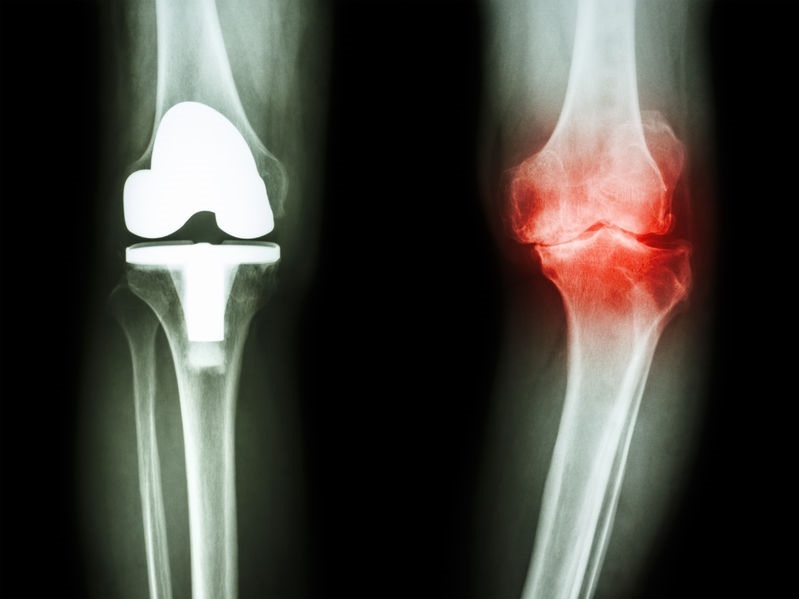

〈変形性膝関節症の根本原因〉

まず、1つ目の原因は骨盤が歪みにあります。骨盤が外側に広がってくると図のように股関節が外に押し出され足全体がO脚に変形していきます。そうすると内側関節が狭くなり軟骨がよりつぶされ擦り減ってきます。

変形性膝関節症のほとんどは膝の内側の痛みから始まります。これはその原因が骨盤の広がりからくるO脚が原因となっているからです。

減ってしまった軟骨を再生することは出来ませんが、関節バランスを整えることにより楽に歩けるようになります。

長い間、痛み止めや注射をしていると変形進み手術しか選択が無くなってしまいます。その様にならないためにも一日も早くご相談ください。